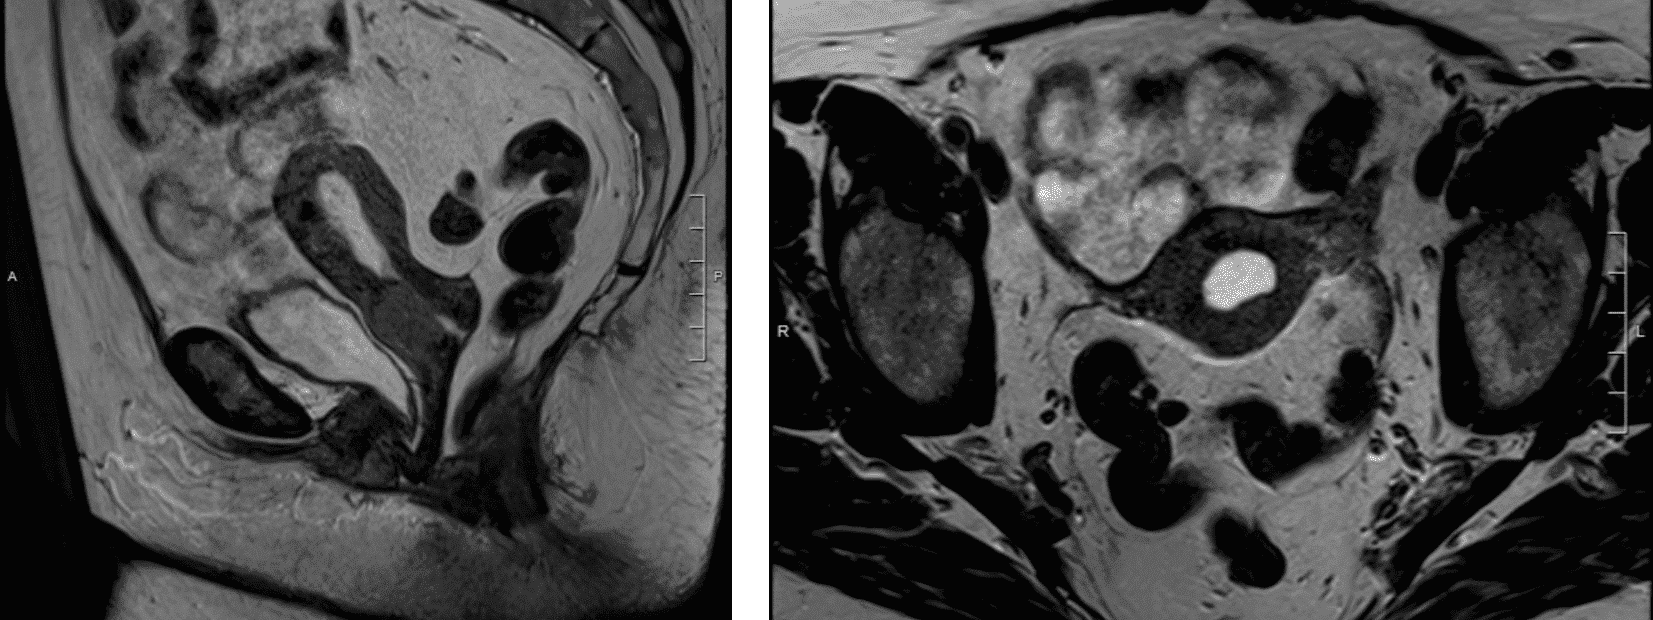

The use of imaging allows for correlation of clinical findings with respect to tumor size and locoregional extension. Furthermore, it allows for evaluation of lymph node metastases. When the prior FIGO staging system, which is based on clinical evaluation only, was compared to operative staging, it was found that patients were understaged in 30%, 25%, and 40% for stage IB, IIB, and IIIB respectively [69]. The ability of MRI and CT to identify lymph node involvement was reported to be 37% and 31%, respectively [70]. Clinical staging had worse sensitivity (29%) than CT (42%) and MRI (53%) for advanced stage disease, which prompted the inclusion of imaging with the most recent FIGO staging. Imaging studies may include chest x-ray, intravenous pyelography, cystoscopy, sigmoidoscopy, barium enema, computed tomography scan, positron emission tomography and magnetic resonance imaging. While MRI and CT are similar in their ability to identify lymph node metastases, MRI is superior in assessing tumor size and parametrial extension (Figure 2) [71, 72]. PET has been shown to be more sensitive (75%) and specific (92%) for para-aortic nodal involvement, which portends a poorer prognosis and overall survival [73-75].

Figure 2. MRI demonstrating extension of a cervical tumor along the anterior vaginal wall (a) and the left parametria (b).